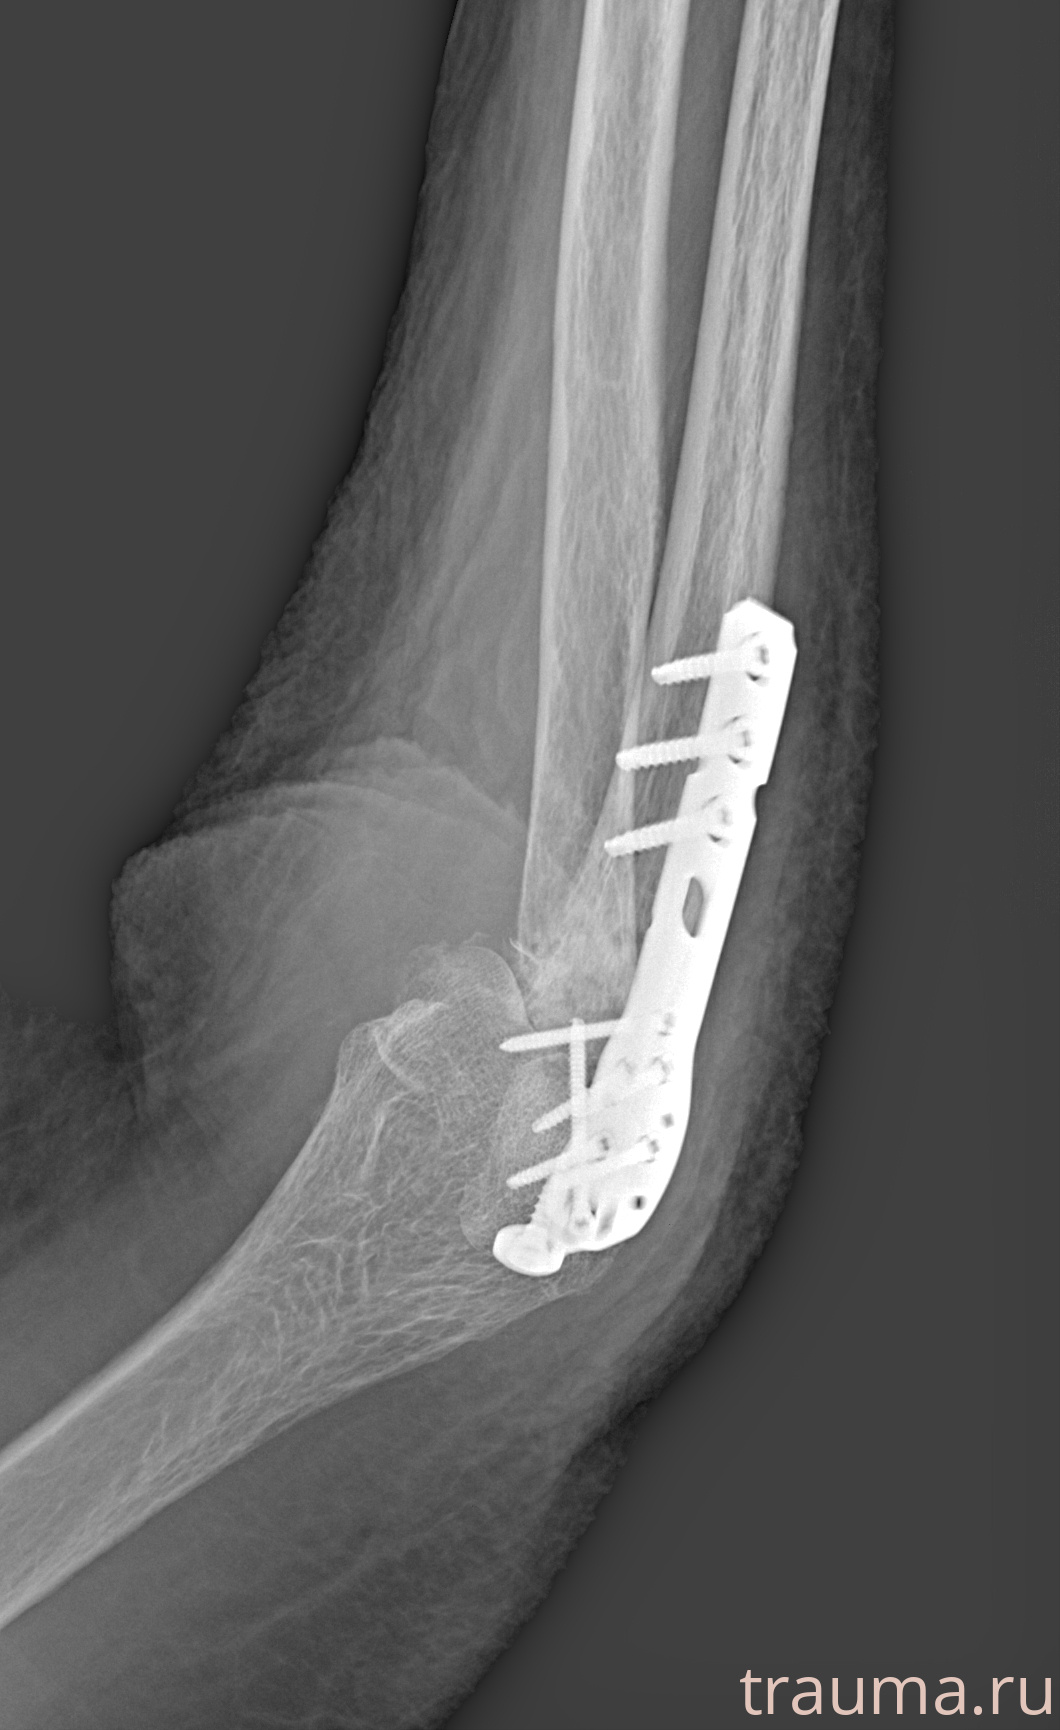

Рентгенограммы